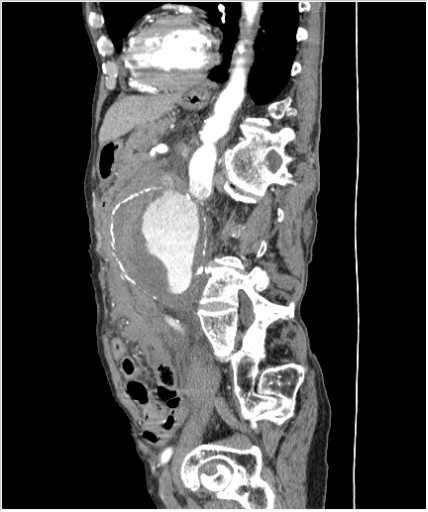

КТ брюшной полости. Мужчина с пальпируемой опухолью в животе

Пациент Т. 64 года, обратился на КТ брюшной полости амбулаторно (!), по направлению семейного врача с диагнозом abdominal mass, буквально: образование брюшной полости.

Huge abdominal aorta aneurism. Simple renal cortical cysts (Bosniak type 1).